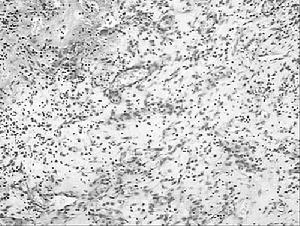

宋玉果在19歲女工肺部發現了數量龐大的納米顆粒面部、脖子和手臂開始劇烈地瘙癢,像“無數隻蟲子在爬動”。同時感覺窒息,像是“被濕紙巾糊住了鼻孔”。 胸悶得“透不過氣來”。

在接下來的4個月裡,肺部出現了更為清晰的納米顆粒。這些黑點數量龐大,不規則地分布在她的肺部。看起來像是蝌蚪狀的精子,或者天空里一閃而過的彗星。從這些納米顆粒中提取出了變異的細胞質和肺上皮細胞。這些肺上皮細胞的染色質發生了嚴重濃縮,邊緣呈現萎靡狀態,細胞的形態特徵基本上呈現新月狀——這些都是細胞死亡的前兆。

專家們使用色譜裝置發現,這種軟聚丙烯酸酯化合物含有丁酸、丁基酯、N-丁基醚、醋酸、正丁醇、甲苯和二氧化碳等。通過電子顯微鏡,宋玉果又有了新發現——直徑約30納米的顆粒。一根頭髮的直徑大約是它的2666倍。